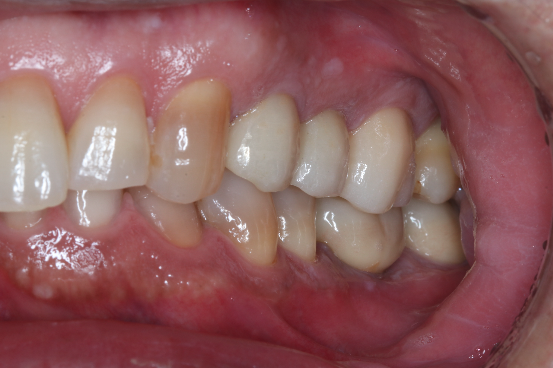

症例②

年齢50代男性

治療期間4ヶ月

治療内容セラミック治療、インプラント治療

治療箇所

インプラント:左下6番

セラミック:左上4番、5番、7番 左下7番 右下6番 右上5番

治療費用950,000円

セラミック治療

インプラント治療